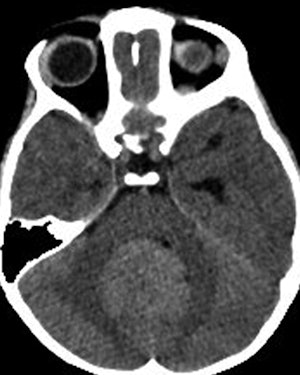

CT scan through posterior fossa and temporal lobes of 3-year-old boy. Radiologist at outside referring institution initially diagnosed hydrocephalus, whereas specialty radiologist at tertiary care hospital recognized posterior fossa tumor as cause of hydrocephalus. All images courtesy of the American Roentgen Ray Society.